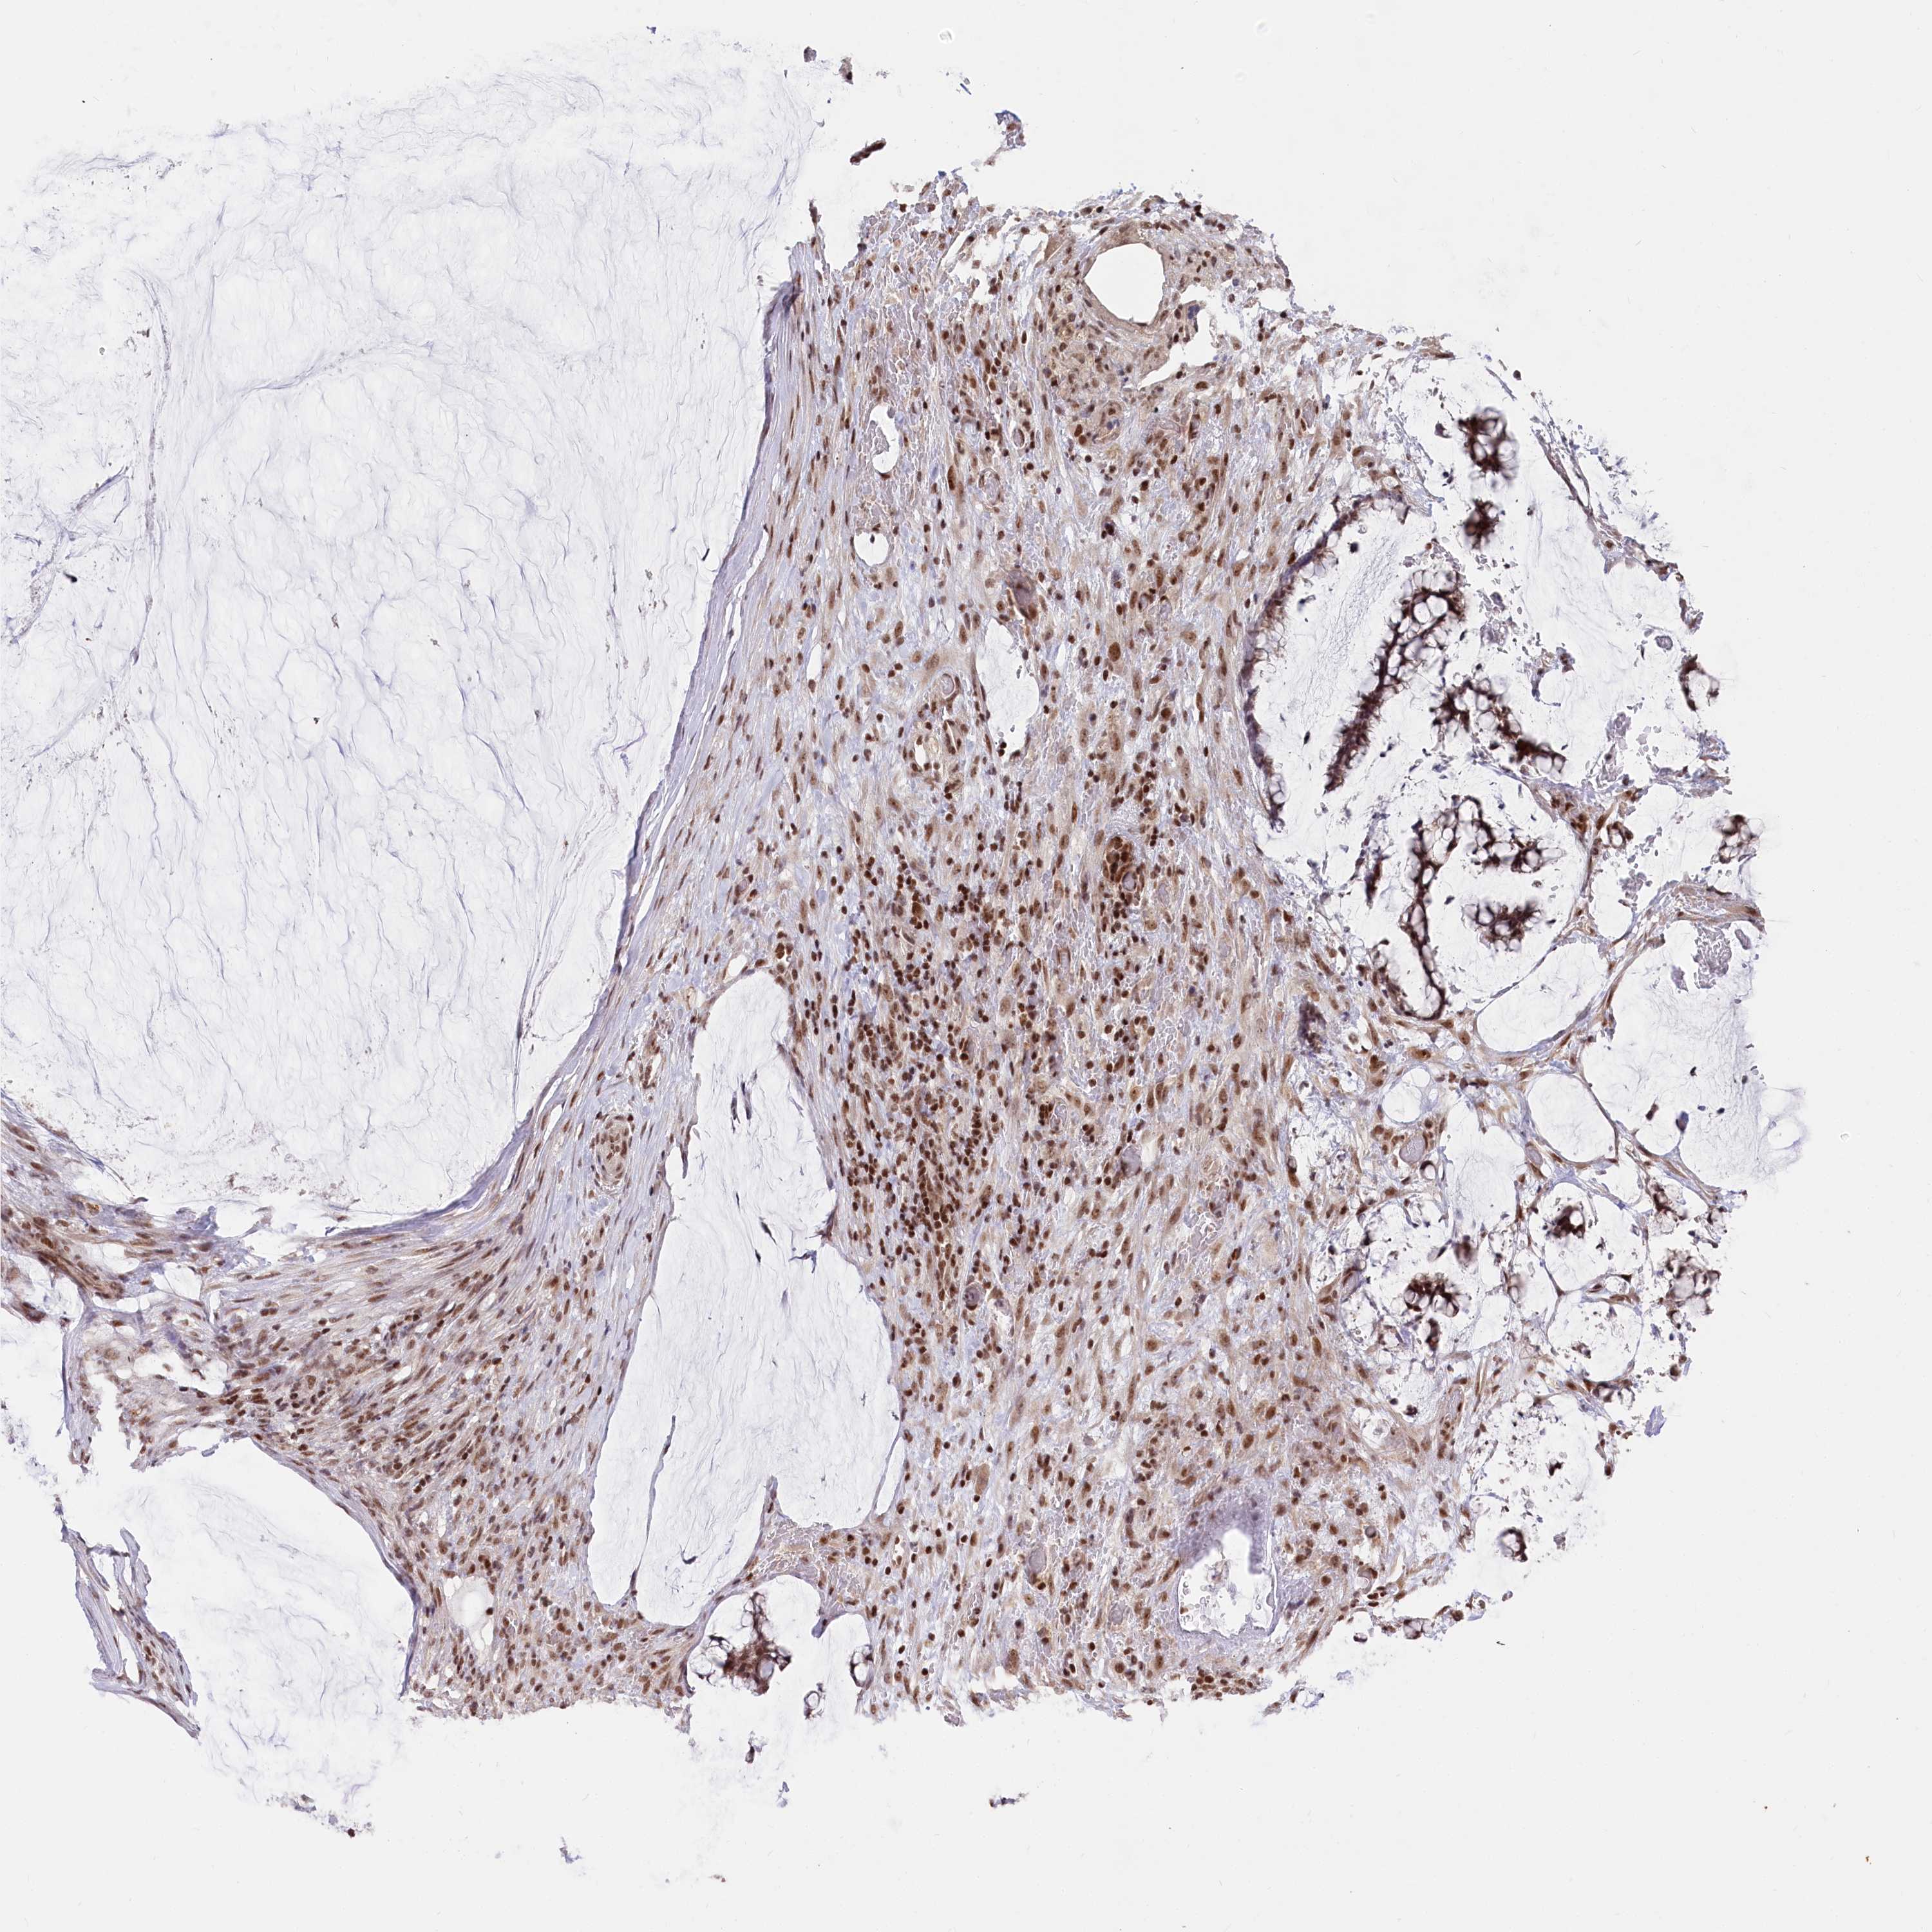

OVARIAN CANCER - Protein expressioni

A mouse-over function shows sample information and annotation data. Click on an image to view it in a full screen mode. Samples can be filtered based on level of antibody staining by selecting one or several of the following categories: high, medium, low and not detected. The assay and annotation is described here.

Note that samples used for immunohistochemistry by the Human Protein Atlas do not correspond to samples in the TCGA dataset.

Antibody stainingi

Antibody staining in the annotated cell types in the current human tissue is reported as not detected, low, medium, or high, based on conventional immunohistochemistry profiling in selected tissues. This score is based on the combination of the staining intensity and fraction of stained cells.

Each image is clickable and will lead to virtual microscopy that enables deeper exploration of all samples and also displays staining intensity scores, fraction scores and subcellular localization as well as patient and tissue information for each sample.

Antibody HPA035568

Antibody HPA037017

Staining

High

Medium

Low

Not detected

Intensity

Strong

Moderate

Weak

Negative

Quantity

>75%

75%-25%

<25%

None

Location

Nuclear

Cytoplasmic/membranous

Cytoplasmic/membranous,nuclear

Cystadenocarcinoma, serous, NOS

Carcinoma, endometroid

Cystadenocarcinoma, mucinous, NOS

Carcinoma, NOS